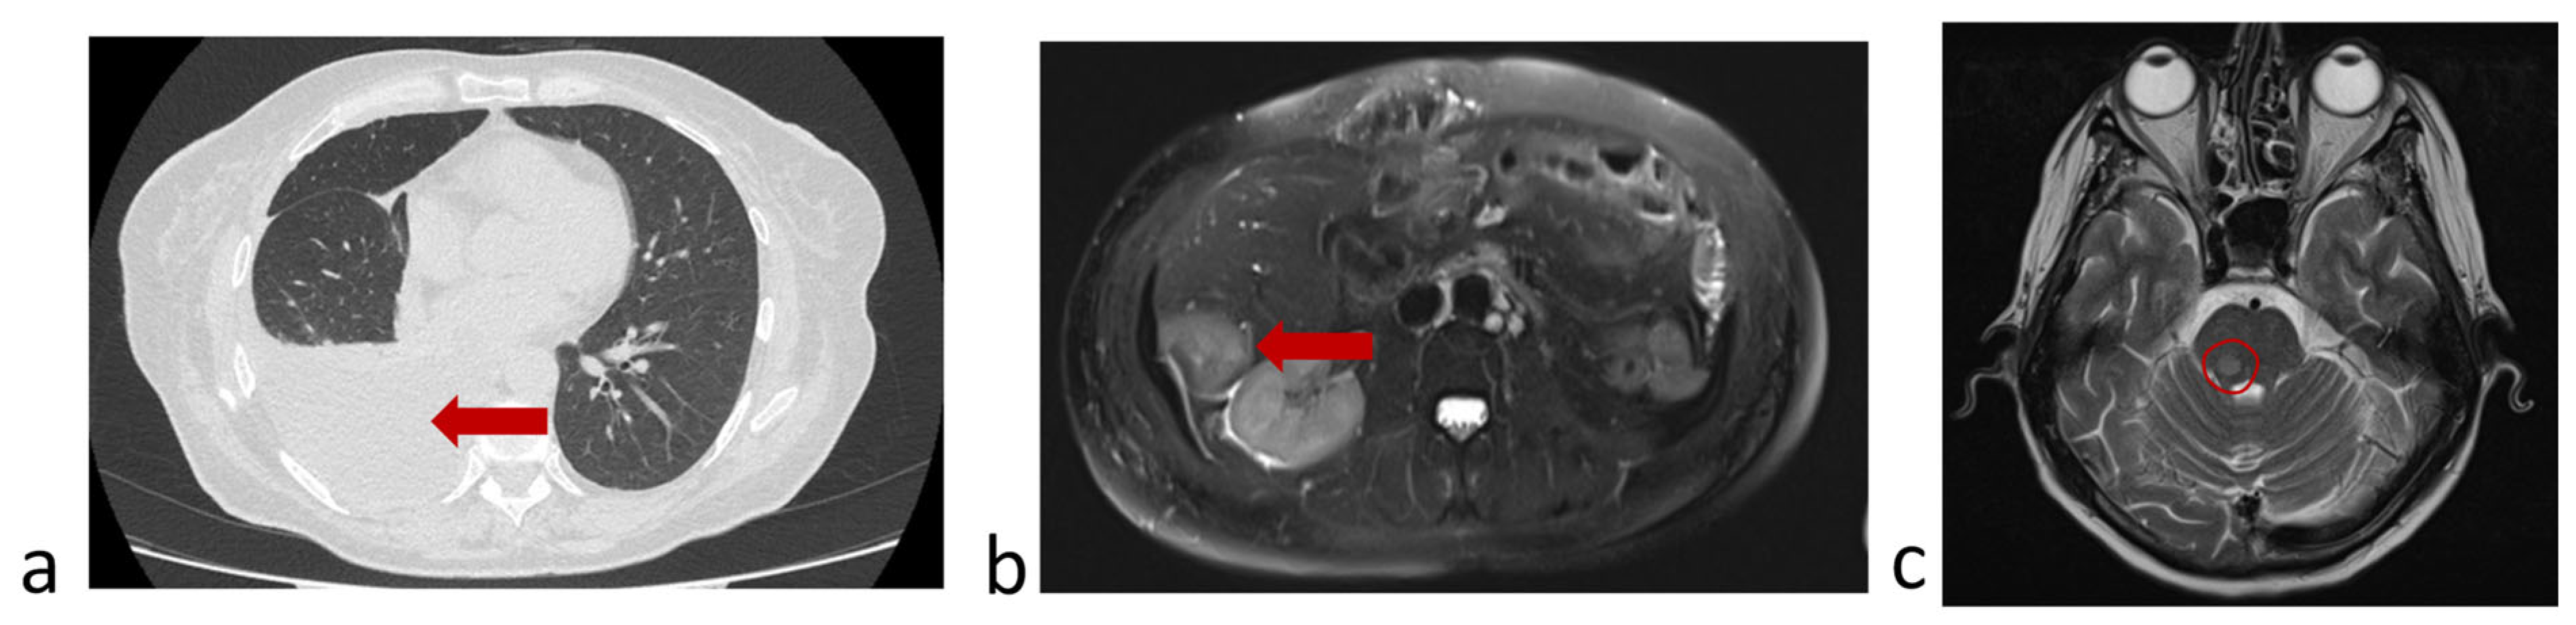

3.6.1. A Clinical Example Demonstrating a Favorable Outcome of the Disease and the Evolution of the Number of CTCs Detected in the Peripheral Blood